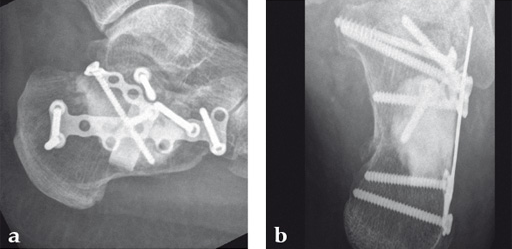

Case 1: A 70-year-old man sustained a Sanders IIA fracture of his left calcaneus.

(Case provided by Michiel Verhofstad, Tilburg, The Netherlands)

After open reduction a gap was left due to impaction of the osteoporotic metaphyseal bone. To support preliminary maintenance of the primary reduction a block of calcium phosphate was introduced beneath the posterior facet. The rest of the gap was filled with Norian drillable. After hardening plate osteosynthesis was performed. Two screws were placed through the fiber-enhanced calcium phosphate. Weight bearing was started 6 weeks later. After 6 months the fracture was healed without secondary loss of reduction. Note that at that time the degradation of the void filler is visible.